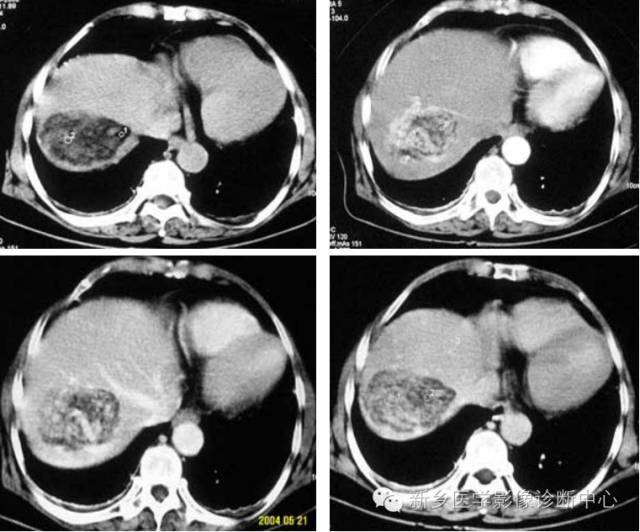

CT表现

1.平扫:肿瘤一般呈低密度,少数呈等密度。

2.动脉期:肝癌血供丰富,动脉期肿瘤明显强化,小肝癌常为均一增强浓染,大肝癌由于内部形成分隔,有不同的血管结构,而成不均匀增强效果,其差别较大。

3.门脉期:呈低密度或等密度。

4.延时扫描为低密度。